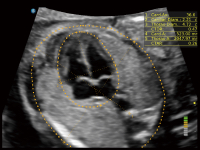

夢(mèng)溪?P80以“關(guān)愛(ài)女性”為基石,提供全方位的解決方案,量身定制以滿(mǎn)足女性的健康需求,涵蓋婦科、生殖健康檢查、產(chǎn)前篩查及產(chǎn)后康復(fù)等領(lǐng)域。